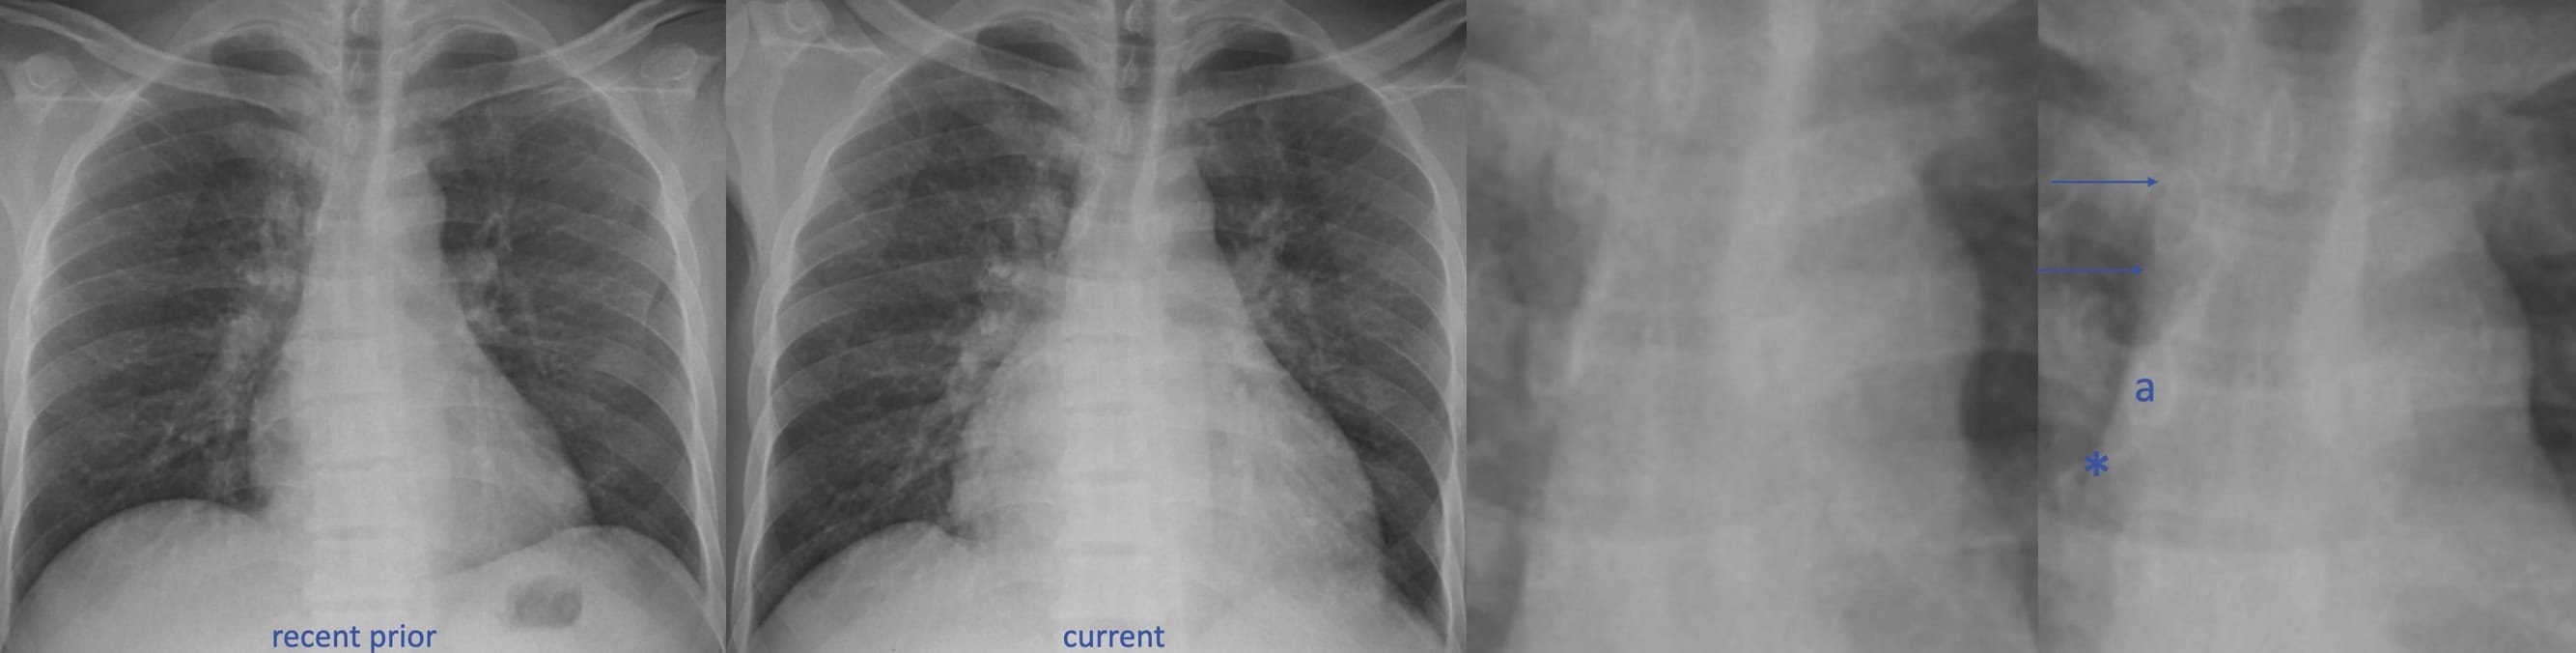

Acute Lung Injury Edema

Two key points enable a distinction between hydrostatic and acute lung injury edema.

• In hydrostatic lung edema, there is (usually) a sequential accumulation of fluid–interstitial, then alveolar.

• In acute lung injury edema, alveolar flooding occurs immediately.

Typical findings in acute lung injury edema

The distribution of edema fluid (consolidation) is typically diffuse and symmetric.

Acute Lung Injury Edema in Acute Respiratory Distress Syndrome

Criteria for the diagnosis of the clinical entity—ARDS—have been revised several times. This excerpt from UpToDate ® is a useful summary.

It’s common to be asked this question by a clinical colleague: “Are the findings consistent with ARDS”? Of course, that’s the wrong question, which should be: “Are the findings consistent with acute lung injury edema?”

Radiologists do not diagnose ARDS, as such!

CT of Acute Lung Injury Edema

Don’t confuse the posterior lung opacities with anything else other than consolidated and —particularly—atelectatic lung. This is potentially so-called recruitable (by different ventilatory strategies) lung.

The concepts of (dorsal) “sponge” and (ventral) “baby” lungs are evocative. The size of the ventral aerated lung in ARDS (with the patient supine) suggests a “baby” lung— as conceptualized by Gattinoni et. al.